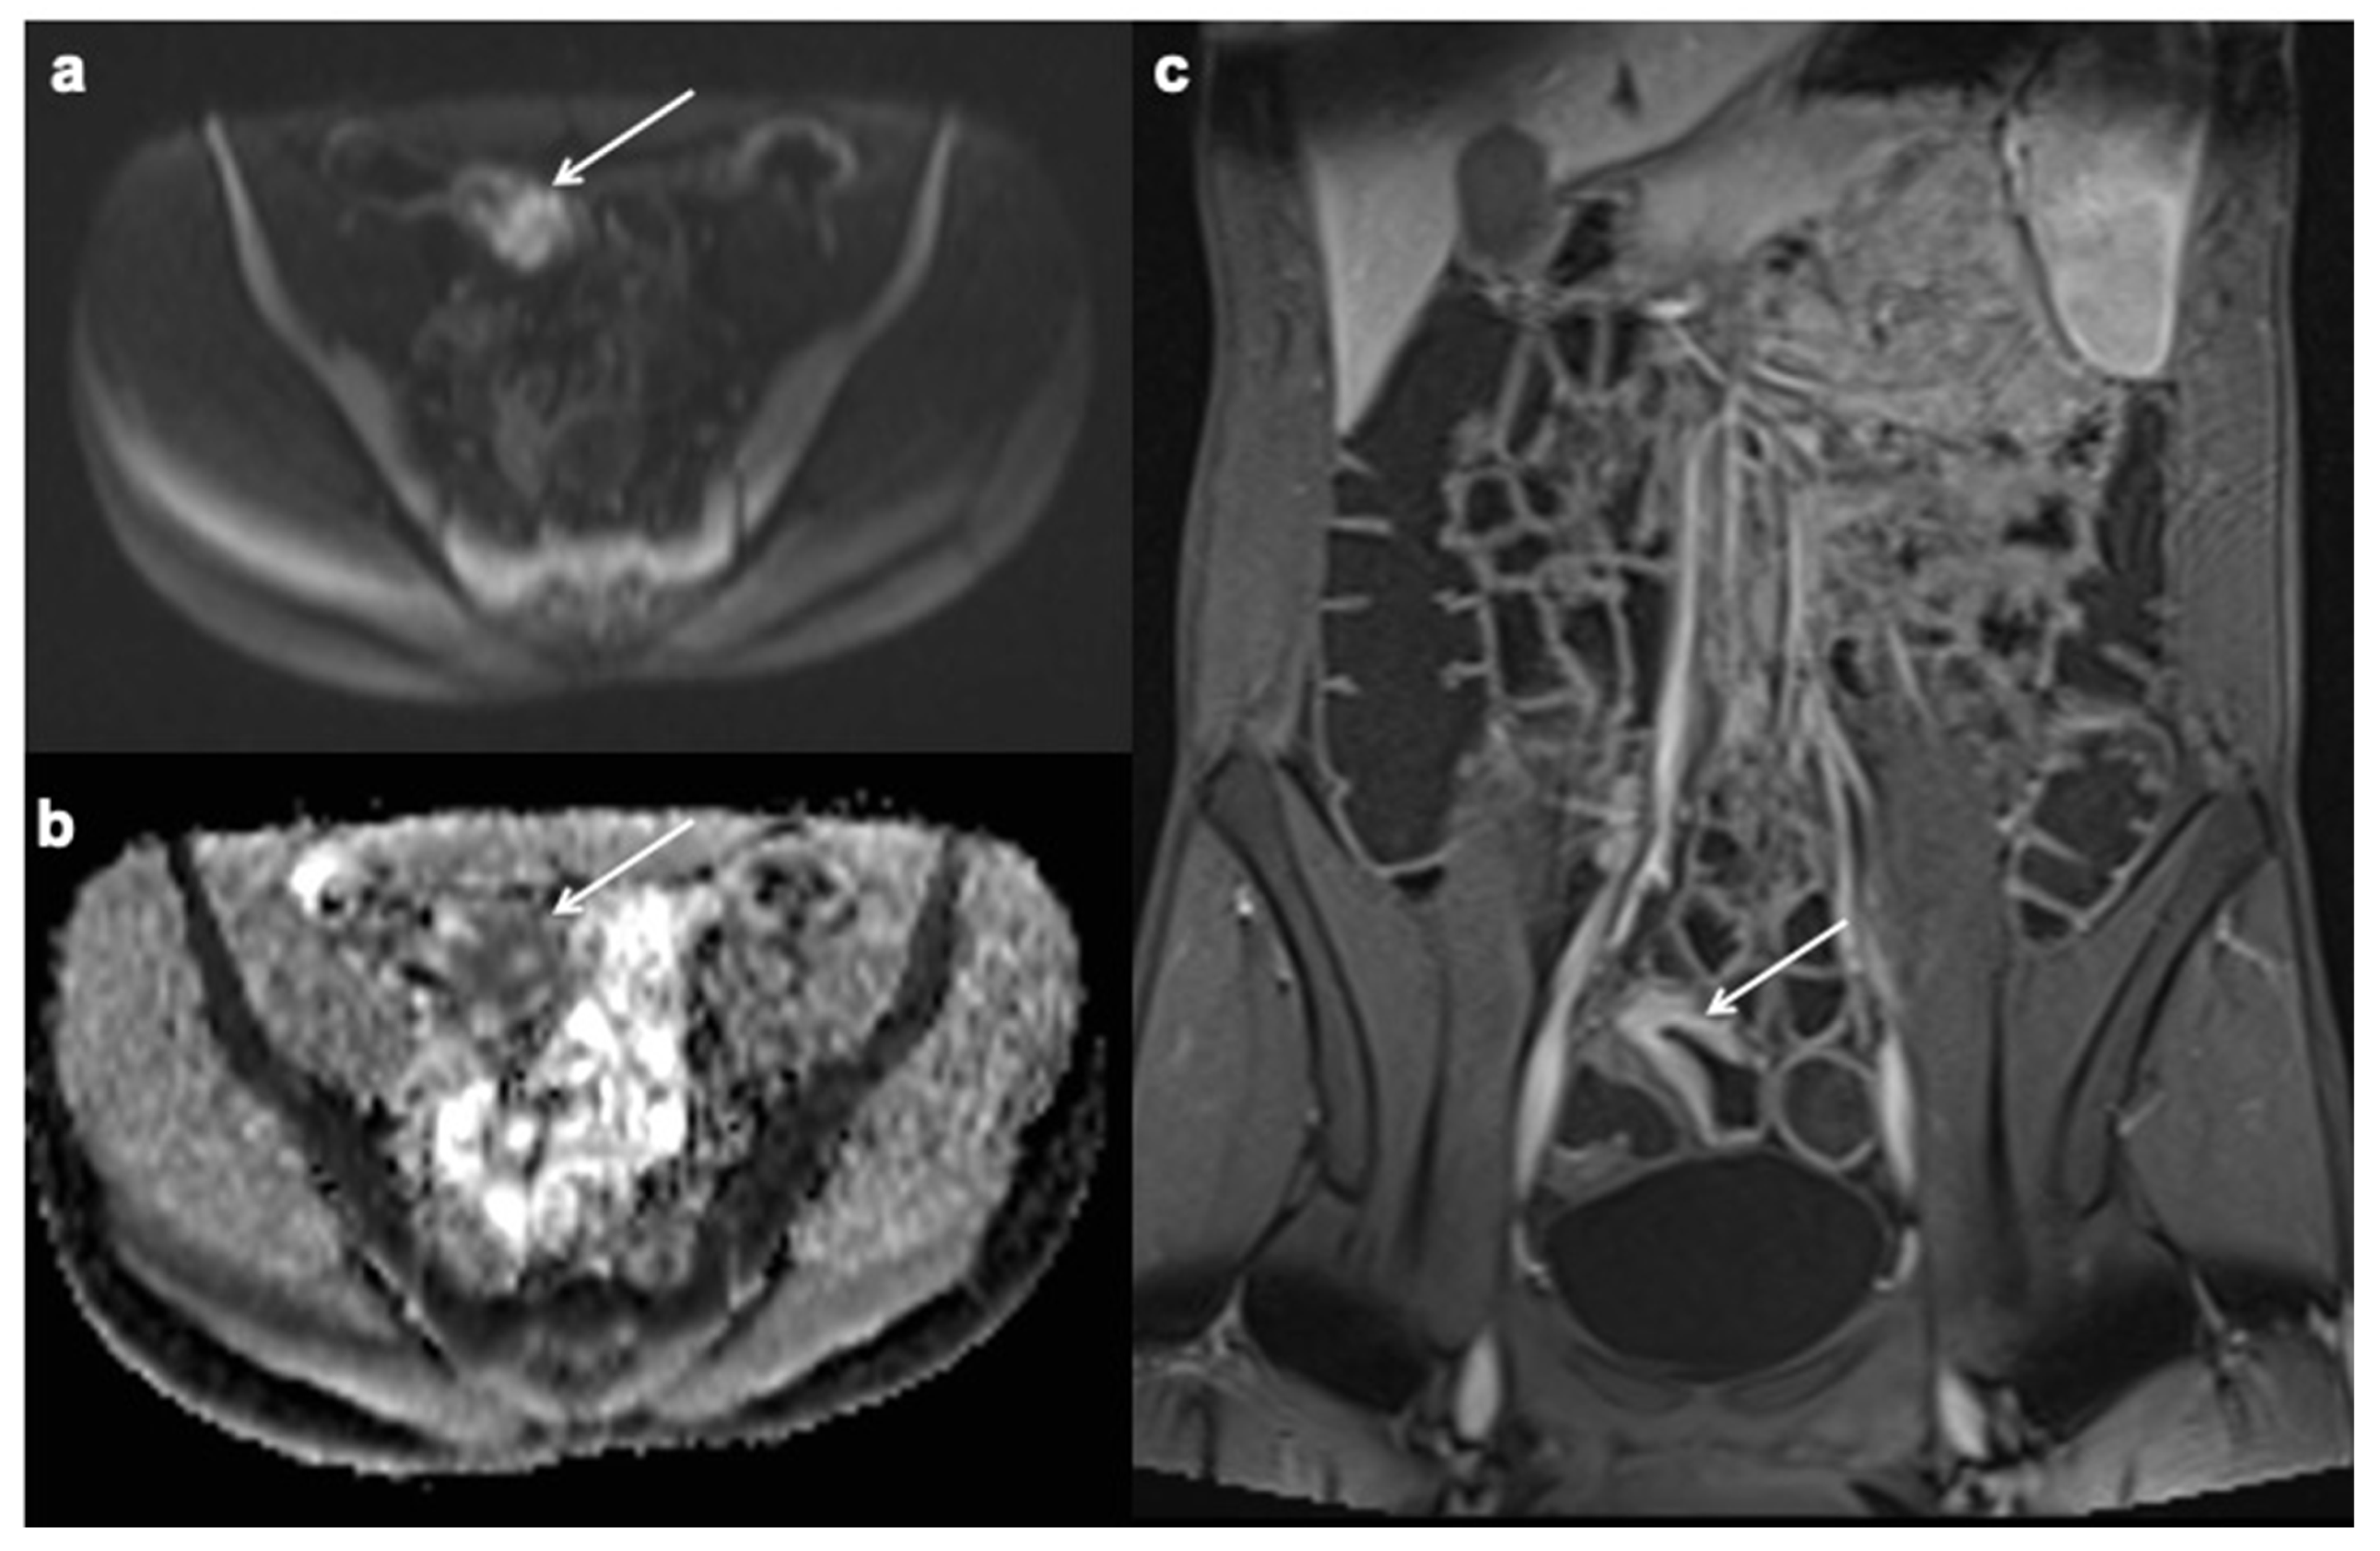

- Oto, A.; Schmid-Tannwald, C.; Agrawal, G.; Kayhan, A.; Lakadamyali, H.; Orrin, S.; Sethi, I.; Sammet, S.; Fan, X. Diffusion-weighted MR imaging of abdominopelvic abscesses. Emerg. Radiol. 2011, 18, 515–524. [Google Scholar] [CrossRef]

- Schmid-Tannwald, C.; Agrawal, G.; Dahi, F.; Sethi, I.; Oto, A. Diffusion-weighted MRI: Role in detecting abdominopelvic internal fistulas and sinus tracts. J. Magn. Reson. Imaging 2011, 35, 125–131. [Google Scholar] [CrossRef]

- Barat, M.; Hoeffel, C.; Bouquot, M.; Jannot, A.S.; Dautry, R.; Boudiaf, M.; Pautrat, K.; Kaci, R.; Camus, M.; Eveno, C.; et al. Preoperative evaluation of small bowel complications in Crohn’s disease: Comparison of diffusion-weighted and contrast-enhanced MR imaging. Eur. Radiol. 2018, 29, 2034–2044. [Google Scholar] [CrossRef]